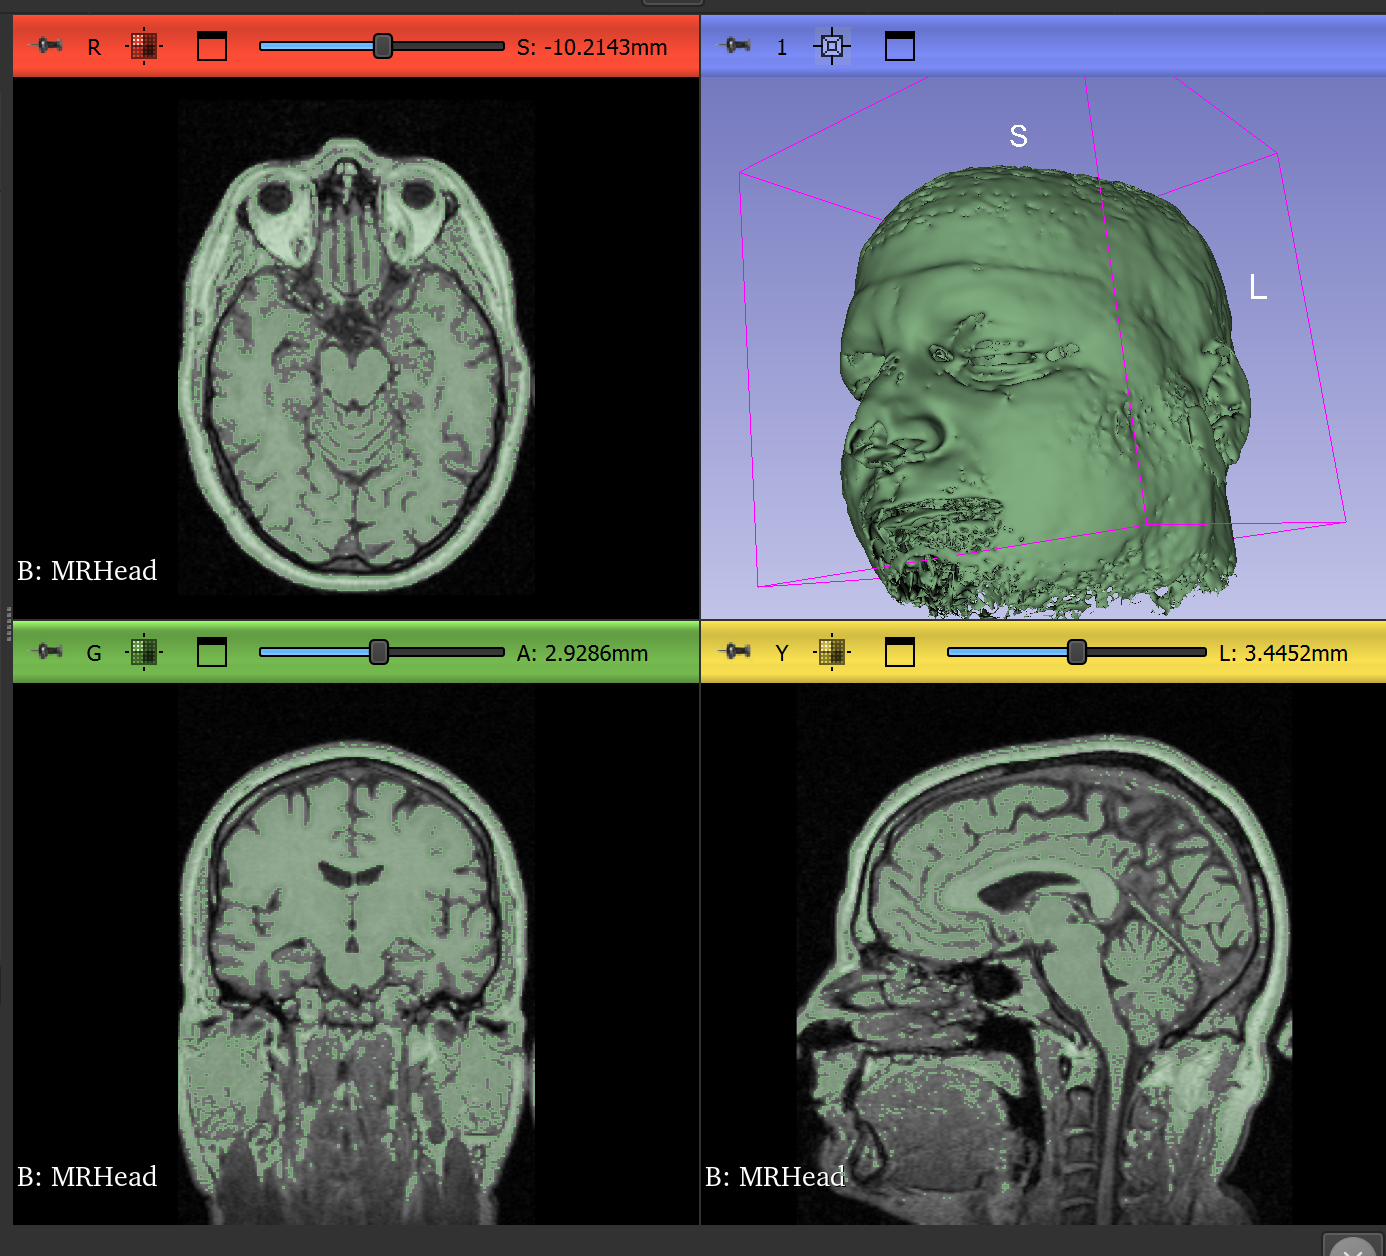

The majority of what I've been doing so far is research into how SwiftUI works, which software applications I can use for creating 3D models, and how to make 3D content interactive in the Apple Vision Pro device. I have a rough mental image of what I want the user to see and be able to do, and I've been keeping that in mind as I read documentation of different features available to me in VisionOS. I found a software called 3D Slicer that I think looks promising. It allows me to import sequences of MRI images at different angles, and create a 3D object out of those sequences (see image). The software has a segmentation tool that allows you to use different methods, such as thresholding or manually painting, to determine which pixels of the MRIs to use in the 3D model. This may be useful for isolating structures of the model in the future if other methods fail, since it requires more manual work ahead of time to prep the scans. I was successfully able to import a sample 3D model into SwiftUI and get it to show up in an Apple Vision simulator, but I'm not yet able to get user interactions (rotate, zoom, etc) to work on it.

Slicer sample data

Slicer's sample MRI data in 3D